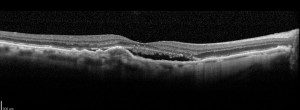

Hyporeflective wedge-shaped band in geographic atrophy secondary to age-related macular degeneration: a little-understood spectral domain optical coherence tomography finding.